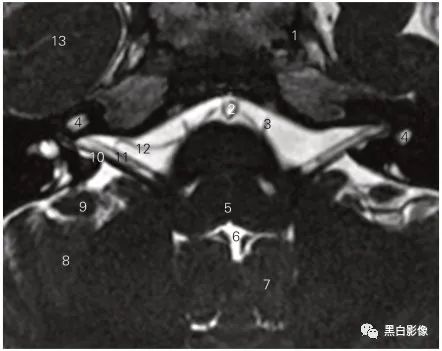

图5-2 经视神经的冠状断层MR T2加权图像

1 眼动脉 ophthalmic artery 2 外直肌 lateral rectus

3 视神经鞘 sheath of the optic nerve

4 筛骨鸡冠 crista galli of ethmoid bone

5 下直肌 inferior rectus 6 内直肌 medial rectus

7 蛛网膜下隙 subarachnoid space 8 视神经 optic nerve

9 眼上静脉 superior ophthalmic vein